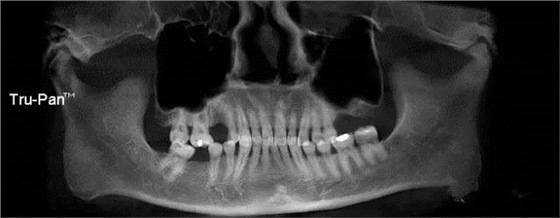

第七圖:斜坡型上頜竇底,圖中右側(cè)上頜竇就是次類型,進(jìn)行上頜竇內(nèi)提升較為困難??筛耐馓嵘中g(shù)。

第八圖:有間隔的上頜竇。上頜竇底中間有骨間隔,通常增大了上頜竇外提升開窗的困難。 北一種植老師主張開兩個小窗,有些醫(yī)生也可以開W型窗,來降低難度。